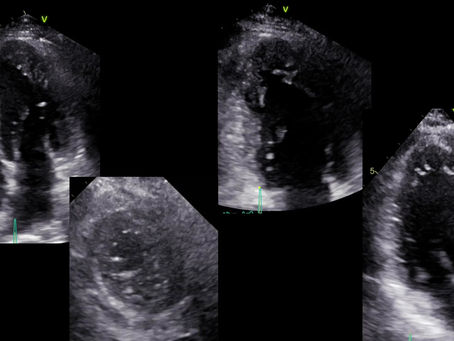

Respuesta al caso de la semana

¿Cuál de las imágenes es compatible con estenosis mitral reumática? La respuesta correcta es A. La imagen de la derecha (B) corresponde a...

ESTENOSIS MITRAL REUMÁTICA

En base a las siguientes imágenes responde la pregunta a continuación: